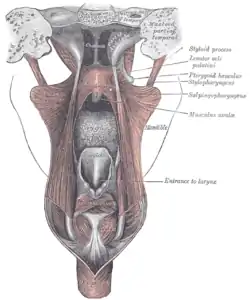

Muscles

The five muscles of the soft palate play important roles in swallowing and breathing. The muscles are:

- Tensor veli palatini, which is involved in swallowing

- Palatoglossus, involved in swallowing

- Palatopharyngeus, involved in breathing

- Levator veli palatini, involved in swallowing

- Musculus uvulae, which moves the uvula

These muscles are innervated by the pharyngeal plexus via the vagus nerve, with the exception of the tensor veli palatini. The tensor veli palatini is innervated by the mandibular division of the trigeminal nerve (V3).[2]

Soft palate without tonsils (after tonsillectomy) Sagittal section of nose mouth, pharynx, and larynx.

Sagittal section of nose mouth, pharynx, and larynx. The mouth cavity. The cheeks have been slit transversely and the tongue pulled forward.